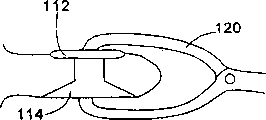

- A61B17/70—Spinal positioners or stabilisers, e.g. stabilisers comprising fluid filler in an implant

- A61B17/7062—Devices acting on, attached to, or simulating the effect of, vertebral processes, vertebral facets or ribs ; Tools for such devices

- A61B17/7065—Devices with changeable shape, e.g. collapsible or having retractable arms to aid implantation; Tools therefor

- A61B17/7068—Devices comprising separate rigid parts, assembled in situ, to bear on each side of spinous processes; Tools therefor